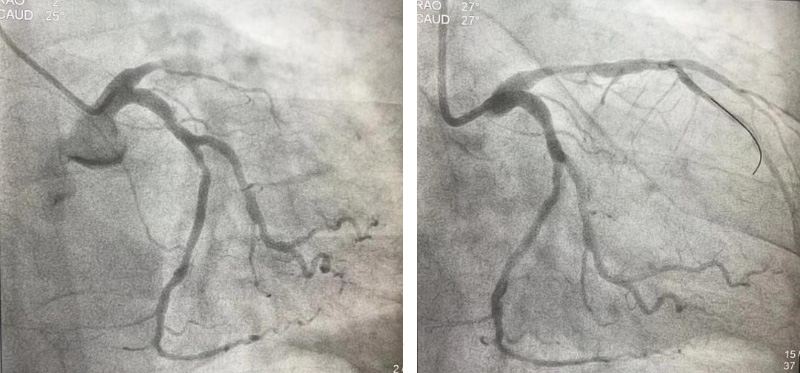

时间紧迫,容不得丝毫犹豫,刘积伦主任团队在告知患者家属相关病情后,立即为患者进行了紧急冠脉造影及支架植入术。手术中,医护人员每一个动作都精准而果断,很快,闭塞的血管被成功开通,恢复3级血流,王先生的心脏重新焕发了生机。